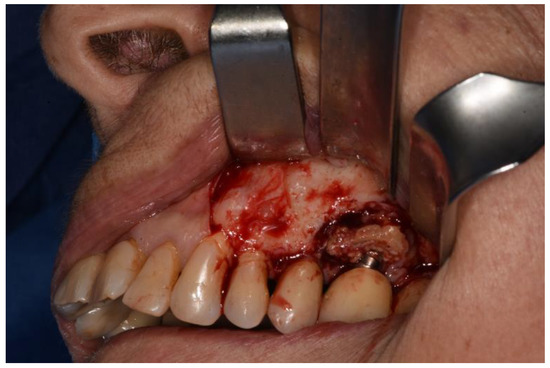

Figure 5. Osteotomy completed polipoid tissue in the maxillary sinus.

Therefore, a full-thickness vestibular flap was set up with medial and distal release incisions to oroantral communication (already present or induced as a result of extraction of dental element, bone implant or excision of lesion due to sinus pathology) and bone defects known. Ostectomy and osteoplasty were performed, if necessary.